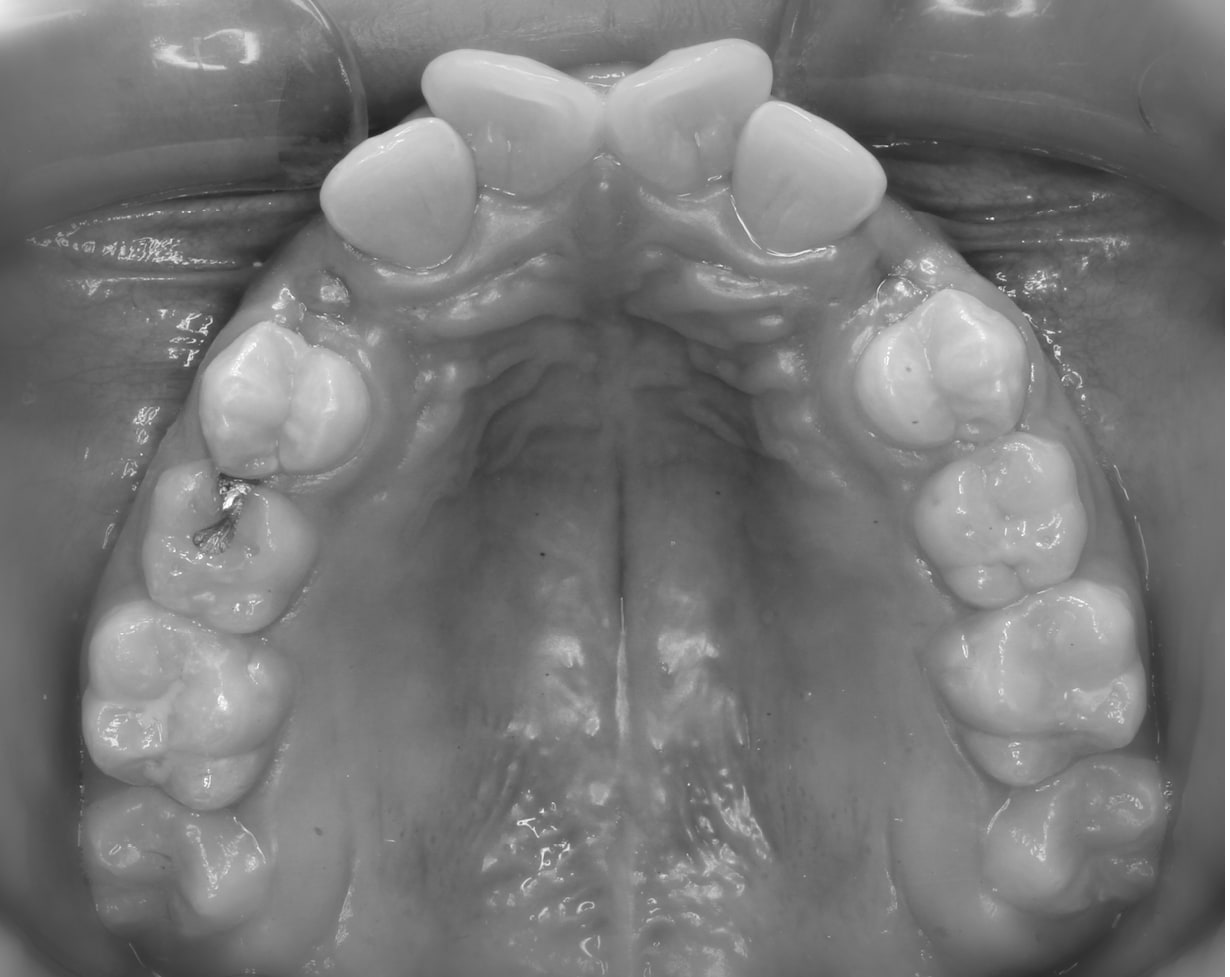

Before

After